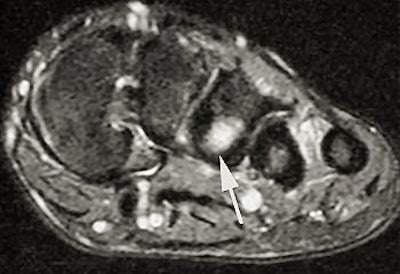

| Delayed image shows increased bone marrow edema and fracture line, base of second metatarsal. |

The follow-up study was led by Dr. Nancy Major, associate professor of radiology at Duke University Medical Center's musculoskeletal division. Her study determined that MRI can effectively predict metatarsal stress fractures by depicting bone marrow edema (a precursor to fractures), thereby enabling the prevention of potential fractures with the use of orthotics.

In this study, 26 male basketball players from Duke and North Carolina Central University in Durham were imaged before and after their 2003 season. Although 19 of 52 feet showed abnormalities with MRI, only one player had complaints of a symptomatic midfoot. The use of an orthotic provided immediate relief, and the player did not subsequently develop stress fractures.

A player experiencing no symptoms, however, did develop a metatarsal stress fracture before he could be fitted for an orthotic ("The role of imaging in the feet in asymptomatic collegiate basketball players," RSNA meeting, December 2, 2004).